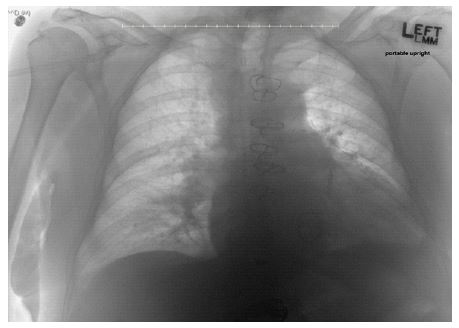

Figure 3: Chest x-ray shows retained coil sitting at the base of the right heart after attempt at coil retrieval.